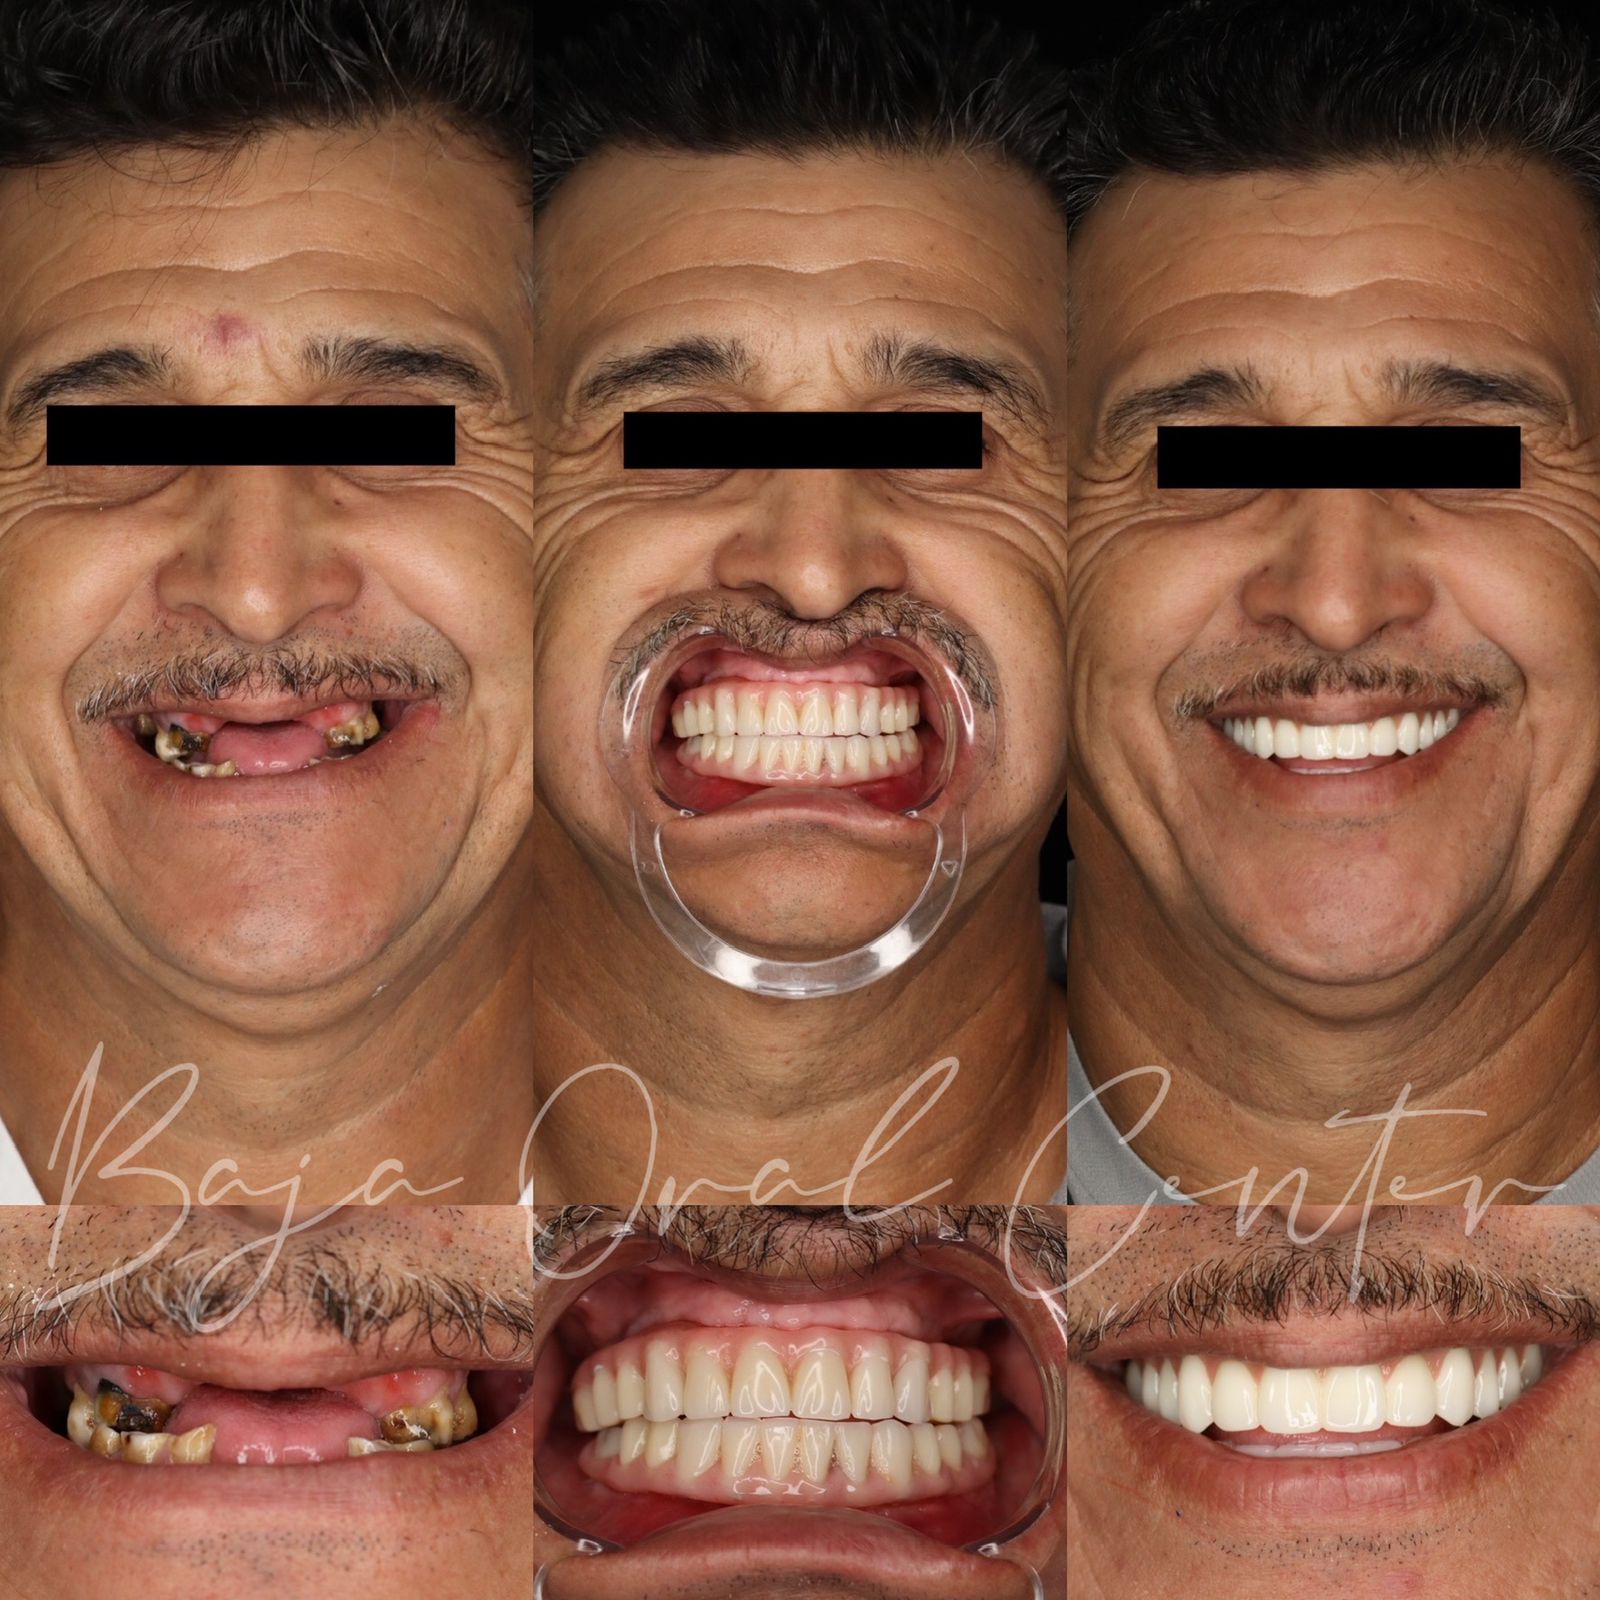

Start your smile transformation in just one trip to Tijuana. Your first phase includes extractions, 4 dental implants per arch, and fixed temporary teeth — all in one day. After 4–6 months of healing, you’ll return for your custom zirconia prosthesis for just $4,000.

Not all smiles need the same solution. That’s why we master every technique

All on 4

•All-on-4 or All-on-6 for stable, proven solutions when there’s an ideal jaw bone.

Phase 1: All on 4 — $7,850

What’s included?

✅ Complete diagnostics & personalized planning (CBCT + records)

✅ Expert placement of 4 implants

✅ Fixed temporary teeth in 72 hours so you can smile & eat right away

✅ Post-op medications & easy recovery support

Phase 2: all in 4 — $4,000

✅ Custom zirconia or premium hybrid final teeth for a perfect, natural look

✅ 5 Year warranty

We proudly showcase the positive experiences of patients who have undergone a full arch rehabilitation with traditional / Corticobasal Implants with Full Arch Baja